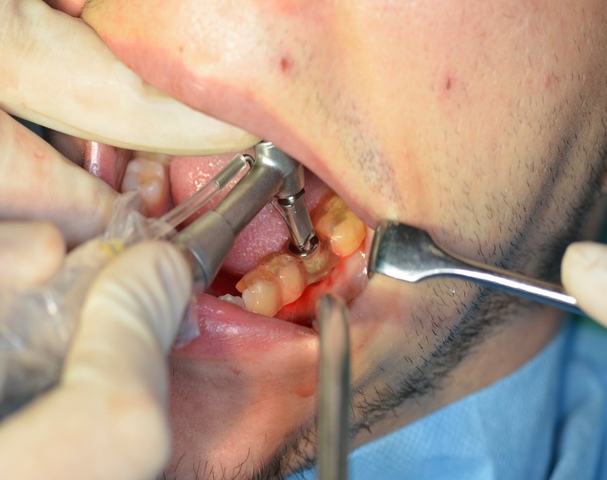

Do Zakładu Chirurgii Stomatologicznej Pomorskiego Uniwersytetu Medycznego zgłosił się ze skierowaniem pacjent 25-letni w celu ekstrakcji zęba 36.

Ryc. 1. Stan kliniczny zęba 36.

Wykonano pantomogram oraz zdjęcie celowane, które ujawniło zmianę okołowierzchołkową przy korzeniu dystalnym. Nie stwierdzono patologii tkanek twardych zębów sąsiadujących z zębem zakwalifikowanym do ekstrakcji, dlatego powzięto decyzję o odbudowie implantologicznej przyszłego braku zębowego (ryc. 1-3).